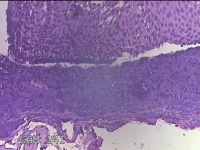

会厌肿物

性别

男

年龄

46岁

临床诊断

1.会厌肿物 2.慢性咽炎

一般病史

发复咽异物感3月余。

标本名称

大体所见

灰白粉红色肿物0.5x0.3x0.2cm一个,表面光滑。

良性病变。